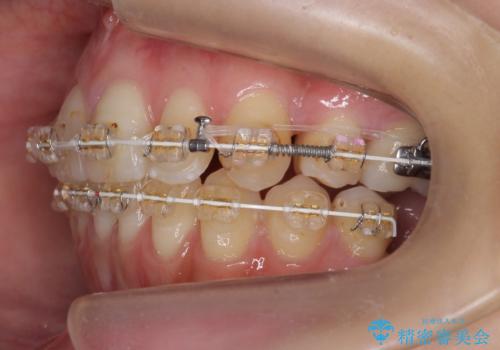

あきらめないで!!虫歯でボロボロでも大丈夫! 非抜歯矯正と虫歯、インプラント治療で見違える歯並びに。

- 矯正治療を希望して来院。

虫歯が多数、また奥歯も欠損してしまっていました。

左下の親知らず、左上の小臼歯が残根状態で一本抜いたほかは抜かずに矯正しました。

①保存不可能な歯は抜歯しそのすき間を矯正で閉じる

②右上の親知らずは活かしてブリッジの支台にする

という、予算がかからないように歯を保存する治療計画を立てました。